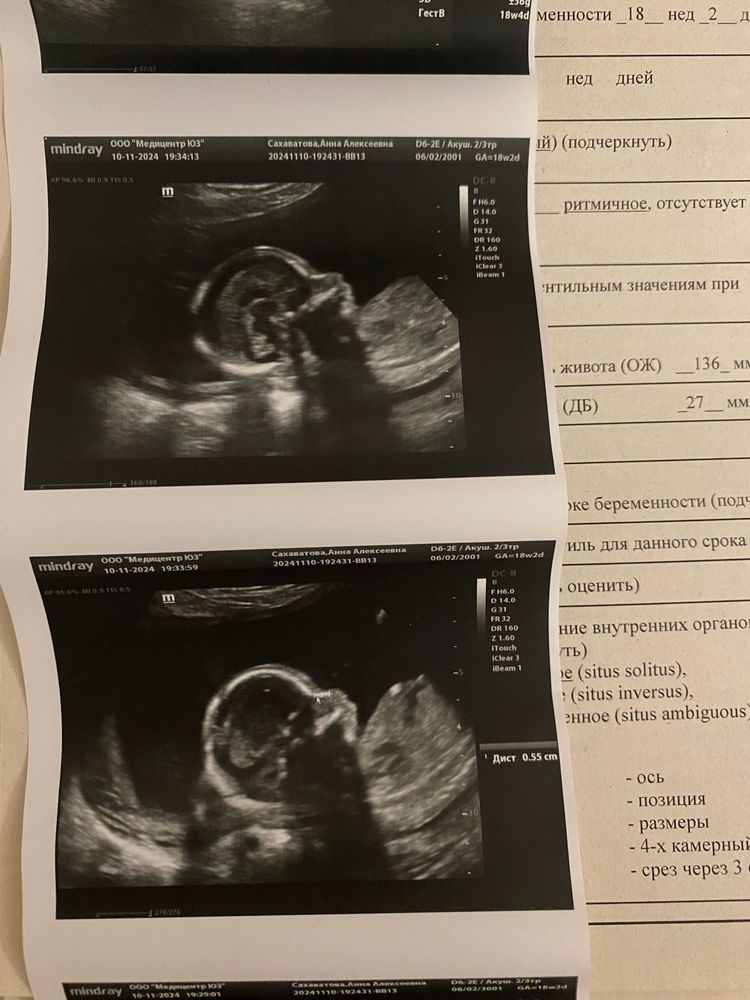

Сходили сегодня на второй скрининг (срок 18 недель и 3 дня), врач тоже сказал, что рано, но почему-то так записали, все равно схожу еще 19 ноября)

Посмотрели на нашу девочку, получили фоточки, правда УЗИ длилось минут 15 (ощутимо по сравнению с первым скринингом, который длился час). Но на первом скрининге я прям целиком видела малышку, а тут она уже настолько большая, что были видны только ее части по отдельности ☺️